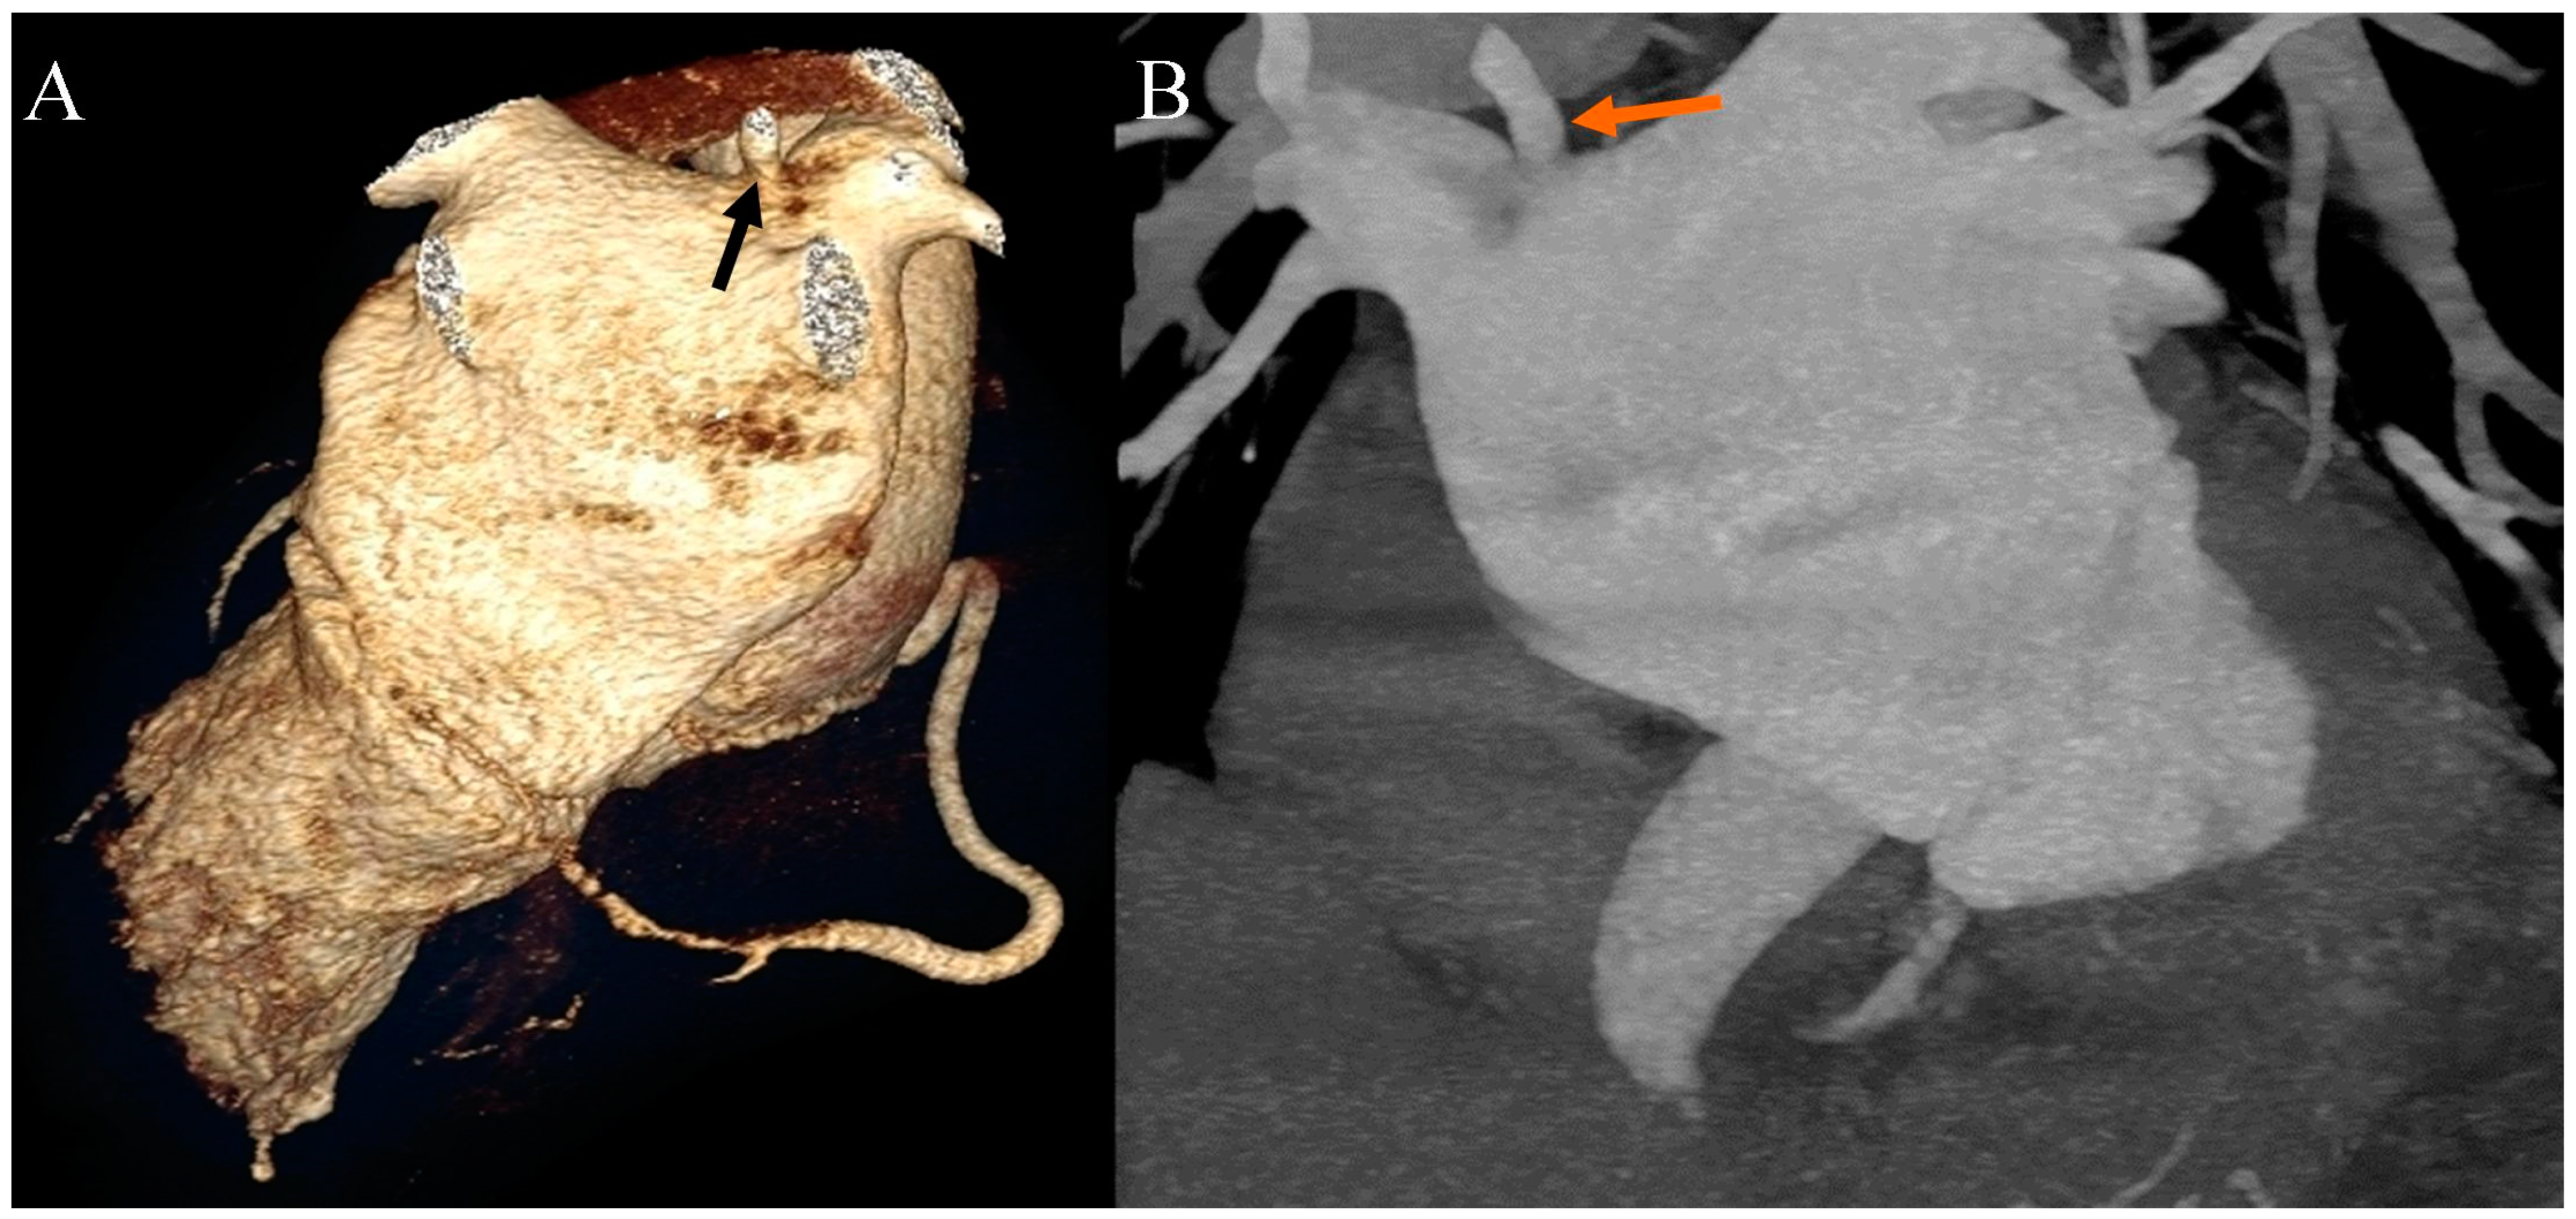

Ehlers–Danlos syndrome (EDS) encompasses a spectrum of heterogeneous, heritable disorders affecting connective tissue. According to the 2017 international classification of EDS, there are 13 subtypes. A rare 14th subtype was found in 2018. Each subtype has unique aspects, and a genetic cause has been identified in all subtypes except hypermobile EDS [1]. Clinical manifestations arise from the pervasive fragility and weakness of the soft connective tissue. Apart from manifestations in the skin, ligaments, joint and internal organs, there are subtypes of EDS which affect blood vessels and cardiac valves. These subtypes confer a higher risk of cardiac valve insufficiency, aneurysms, dissections, or ruptures of arteries, including coronary ruptures [2]. The estimated prevalence of EDS approximates 194.2 cases per 100,000 individuals [3]. Here, we present a case of a 34-year-old man with normal body weight, with hypermobile EDS, type 2 diabetes mellitus, chest deformity, aortic valve regurgitation, and aortic bulb aneurysm characterized by an axial diameter measuring approximately 5 cm (Figure 1). The patient had severe rotational scoliosis of the Th-L spine, with a significant deepening of the thoracic kyphosis and lumbar lordosis. There was a decrease in the AP dimension of the chest, a deformation of the ribs with a decrease in the width of some intercostal spaces, and a secondary widening of the width of other intercostal spaces. The patient underwent elective spine surgery to correct severe rotational scoliosis of the T-L spine. After postoperative rehabilitation, the patient underwent a thorough assessment of eligibility for aortic bulb aneurysm and aortic valve replacement surgeries. Consequently, a coronary computed tomography angiography (CCTA) was performed five months after the spinal surgical intervention. The CCTA revealed an absence of the left main (LM) and the right coronary artery (RCA) dominance. Significantly, the left circumflex artery (LCx) exhibited an ectopic origin from the right sinus of the valsalva, demonstrating a retroaortic course in the proximal segment and a typical course in the distal segments (Figure 2). Furthermore, the presence of a coronary–pulmonary arterial fistula (CPAF) in the CCTA was visualized. A vessel with an approximate diameter of 0.3 cm originated from the right sinus of the valsalva and progressed anteriorly and then towards the left, traversing anteriorly to the right ventricular outflow tract. Thereafter, this vessel was visible to the left of the main pulmonary artery, ultimately divided into multiple narrow segmentally aneurysmally dilated and tortuous fistula vessels. The fistula vessels showed communication with the proximal segment of the main pulmonary artery (Figure 3). Moreover, the imaging revealed the presence of an additional right pulmonary vein (Figure 4). The CCTA revealed calcifications within the aortic valve. The patient received a qualification card for surgical treatment, was informed about the high surgical risk, and is awaiting the operation.

Figure 4. Coronary artery computed tomography angiography. Accessory right pulmonary vein. (A) Volume-rendering technique reconstruction. Posterior view. The arrow indicates the accessory right pulmonary vein on the upper wall of the left atrium. (B) Maximum intensity projection reconstruction. Anterior view. The arrow indicates the accessory right pulmonary vein on the upper wall of the left atrium.